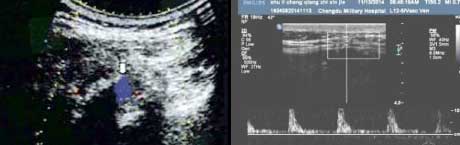

一、发现AS肌腱端炎改变,定性确诊疾病所属

肌腱端炎是AS的基本病理改变,但由于缺乏典型炎症表现(红、肿、热),临床很难早期诊断肌腱端炎。肌骨超声以其敏感度很高的非侵入性检查方法,可提供炎性肌腱异常血流动力学方面的信息,如血流方向、速度及阻力情况等,对血流信号进行定量分析,在强直早期精准判定肌腱炎存在。并通过观察肌腱是否增厚、回声强弱、肌腱周围组织水肿及滑膜肿胀程度,反映关节滑膜及肌腱的病理改变、提供AS炎症活动度评估病变,为患者早期治疗提供帮助。

血流信号

骶髂关节内部增厚的关节表面呈点状血流信号,可见多个小动脉点状血流信号。